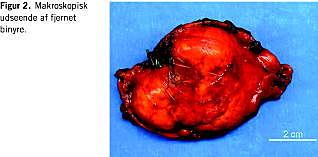

På denne baggrund konkluderede man, at patienten havde ACTH-uafhængigt Cushings syndrom med bilateral binyrebarkhyperplasi. Der blev herefter foretaget laparaskopisk fjernelse af den største binyre. Den operative og postoperative periode forløb ukompliceret. Den fjernede binyre beskrives patologisk som et citrongult, ægformet kapselbeklædt vævsstykke ca. 7 × 6,5 × 6 cm med enkelte små gullige noduli beliggende i fedtvævet (Figur 2 ).